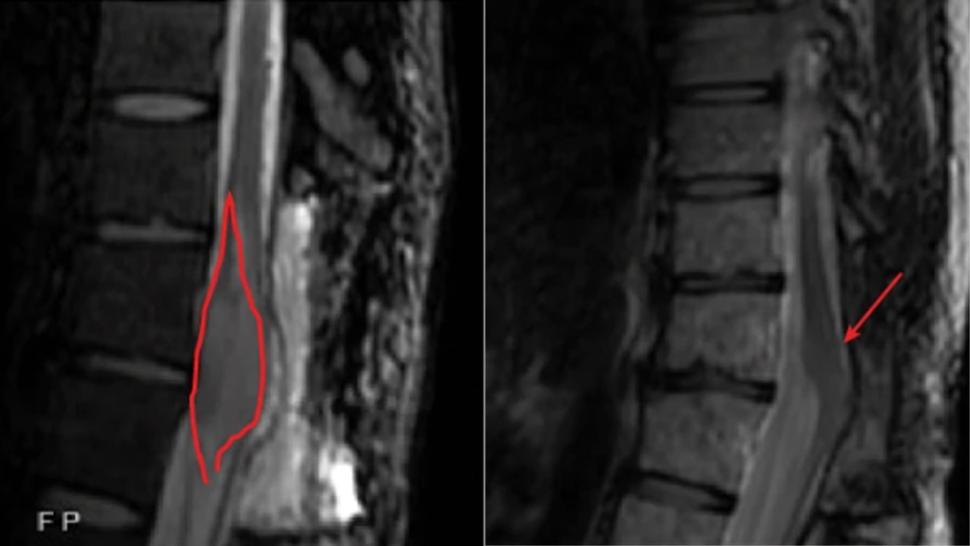

A before and after imaging scans showing a near complete response of a tumor in the spinal cord.

Imaging scans of a patient with a tumor in the spinal cord (left panel, red outline) whose tumor shrank by 90% (right panel, arrow) 9 months after starting GD2 CAR T-cell therapy.

After a follow-up period of 2.5 years after the first treatment, tumors shrank by more than half in 4 of the 9 patients who had initially responded to the treatment, including one patient whose tumor disappeared entirely (a complete response) and has not returned.